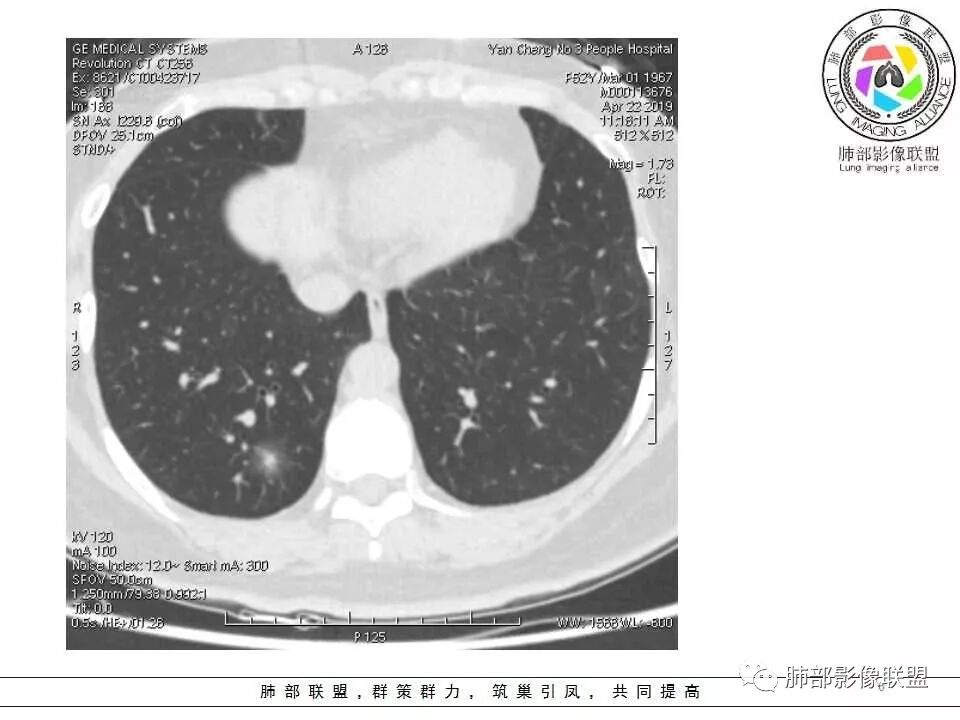

晨读:52f,体检发现右下肺结节,空洞、周围晕征(磨玻璃),局部血管影增粗,考虑1.真菌感染;2.GPA或不典型单发转移待排。

晨读:体检发现肺部结节,胸部CT:右下肺混合密度结节,结节中心空泡,壁光滑,结节边缘模糊,软毛刺,结节血管相对清楚,考虑良性结节可能,抗炎后复查。

右下肺混合磨玻璃结节,其内见空洞,空洞壁光滑,结节周围可见晕征,可见增粗血管,首次体检发现患者无症状,还是建议抗炎2周,1个月后复查,鉴别腺癌。

体检发现肺部结节,右下肺混合密度结节,结节中心空泡,壁光滑,结节边缘模糊,血管在结节内增粗,矢状位前基底段还有一片磨玻璃影,所以考虑良性结节可能,炎性肉芽肿?抗炎后复查。腺癌合并炎性改变待排。

晨读:中老年女性,体检来诊。右肺下叶后基底段近胸膜下mGGN,其内实性成分似见毛刺及分叶,并见空泡征,周围GGO边界清楚,近肺门端见血管影伸入病灶并略显扩张,病变与支气管关系观察欠佳。多考虑恶性,腺癌可能性大。鉴于首次检查,常规建议抗炎治疗后复查,观察病灶变化情况,再决定下一步诊疗方向。

右下叶后基底段混合密度结节,边缘磨玻璃模糊,晕征,中心实性成分似有多个小结节融合,收缩力不明显,中心空泡样改变内缘光滑,考虑小空洞,综合考虑良性炎性结节,隐球可能,结核与曲霉待鉴别。抗炎后复查或穿刺活检。

右肺下叶基底段胸膜下小结节,周围模糊晕征,其内光滑囊腔影,考虑小空洞,其内血管走形自然,周围软毛刺,常规考虑炎性结节,隐球可能性大,建议抗感染后复查,鉴别粘液腺癌。